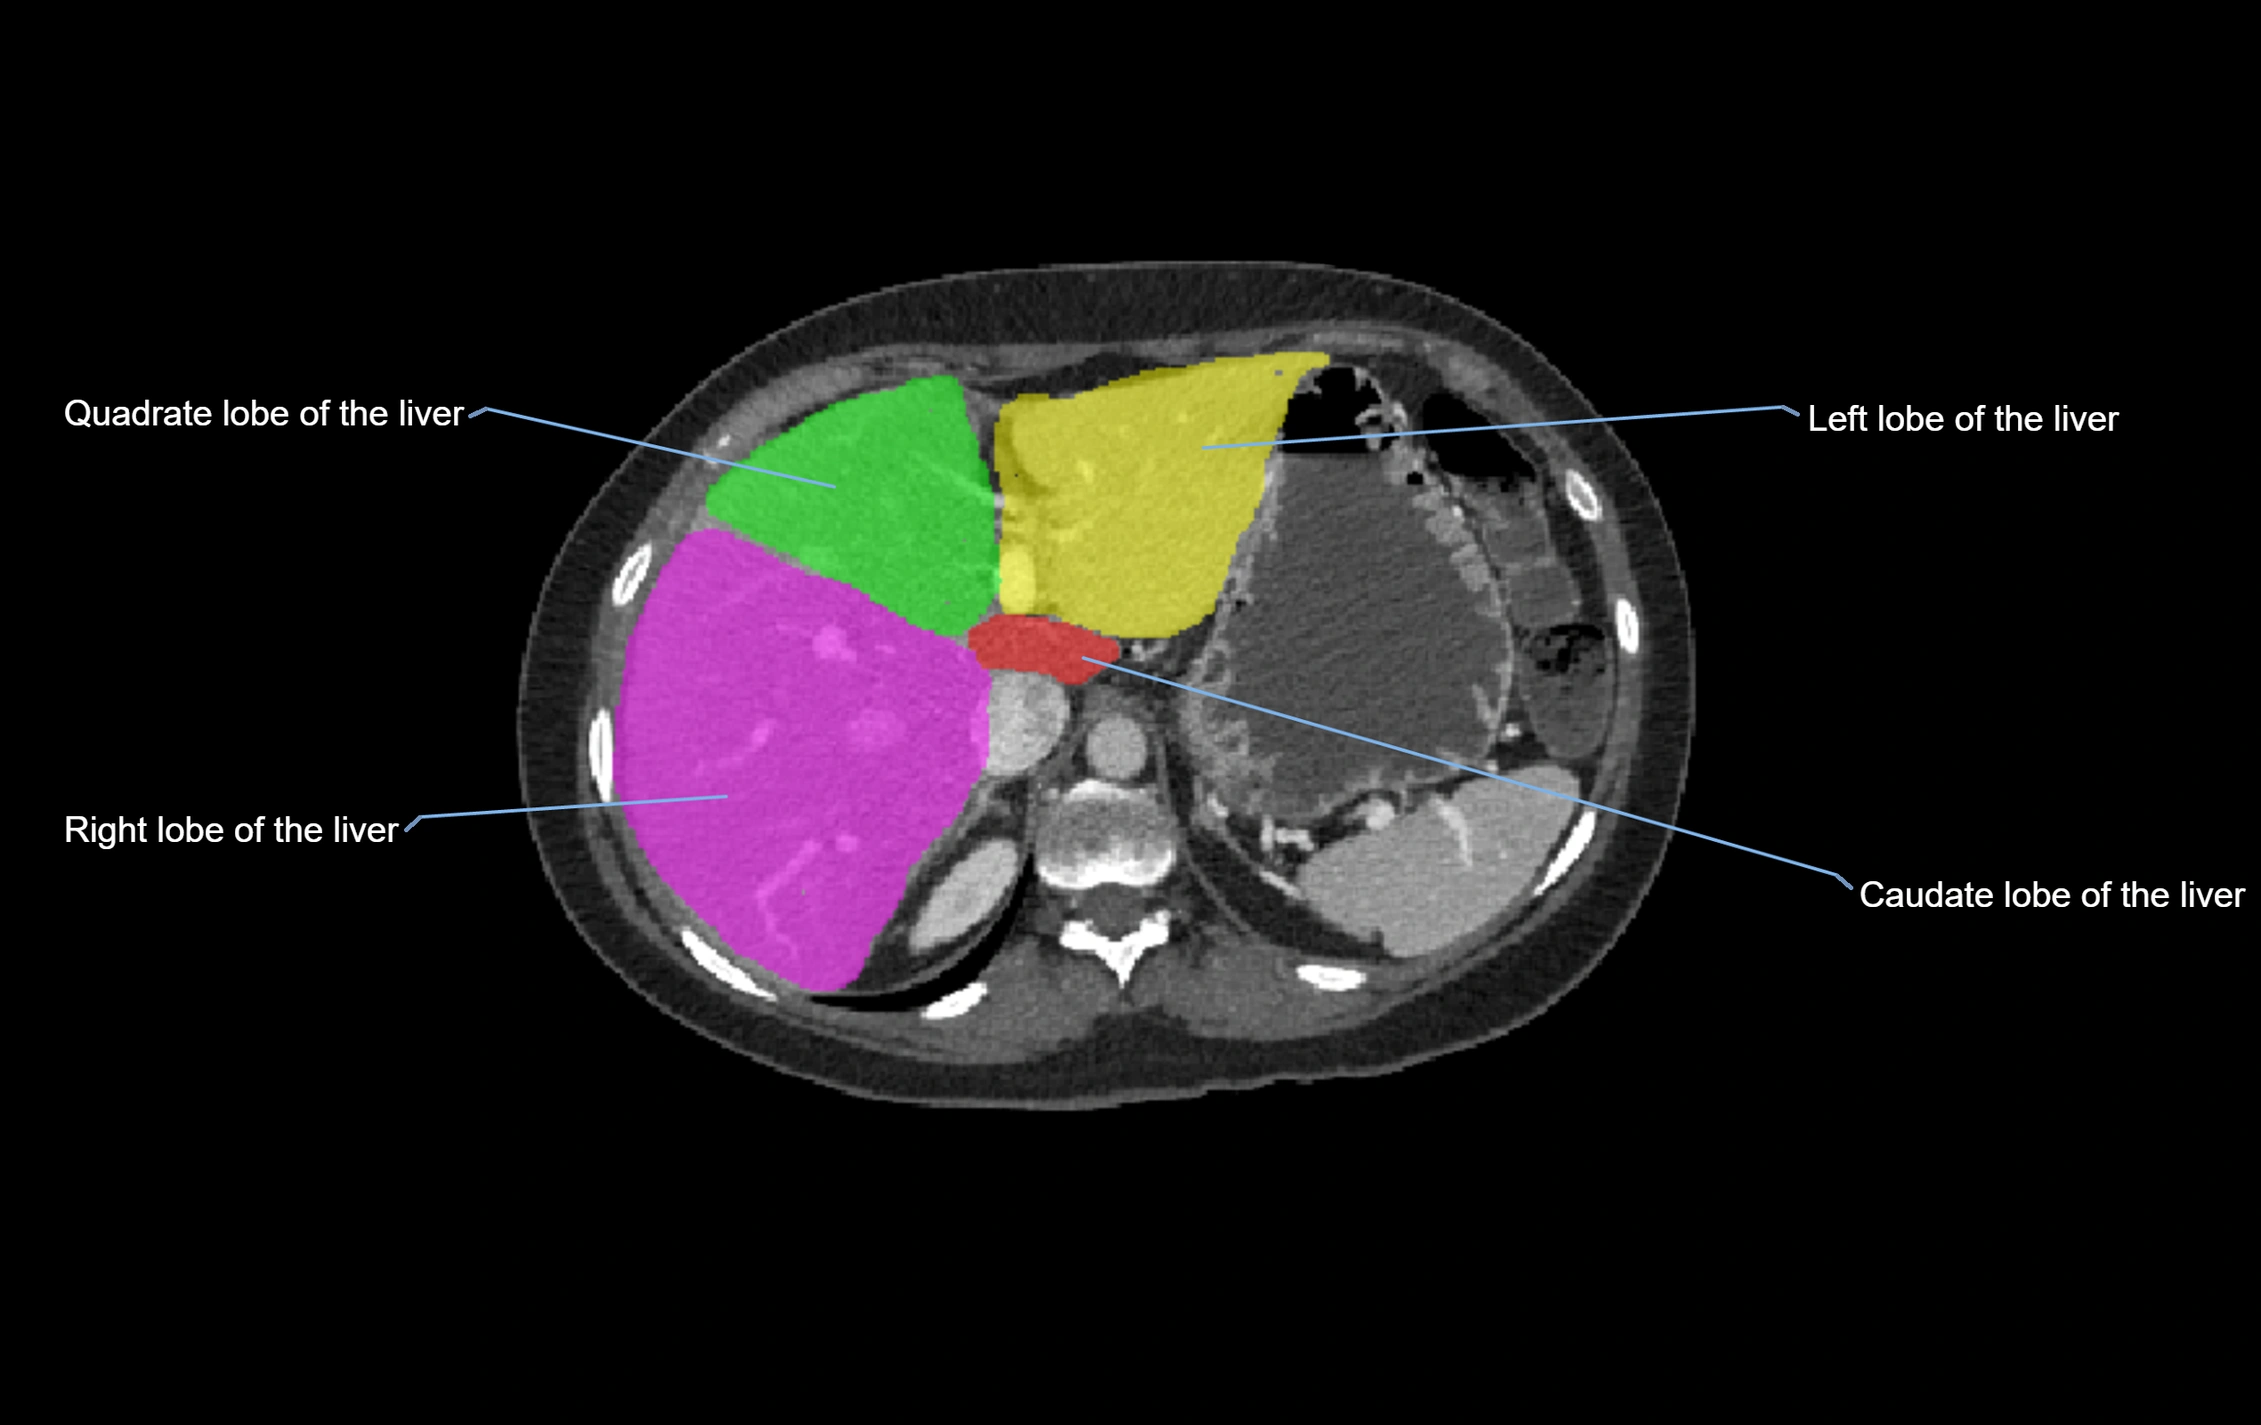

The caudate lobe of the liver is a distinct anatomical subdivision of the liver, designated as segment I in Couinaud’s classification. It lies on the posterior surface of the liver, between the fissure for the ligamentum venosum (left boundary) and the groove for the inferior vena cava (IVC) (right boundary). Superiorly, it is related to the posterior liver surface, and inferiorly it is separated from the left lobe by the porta hepatis.

The caudate lobe is unique because it receives dual portal venous and arterial inflow from both the right and left portal veins and hepatic arteries. It also has independent venous drainage directly into the IVC via multiple small hepatic veins, unlike other lobes that drain through the three main hepatic veins.

CT Image

image